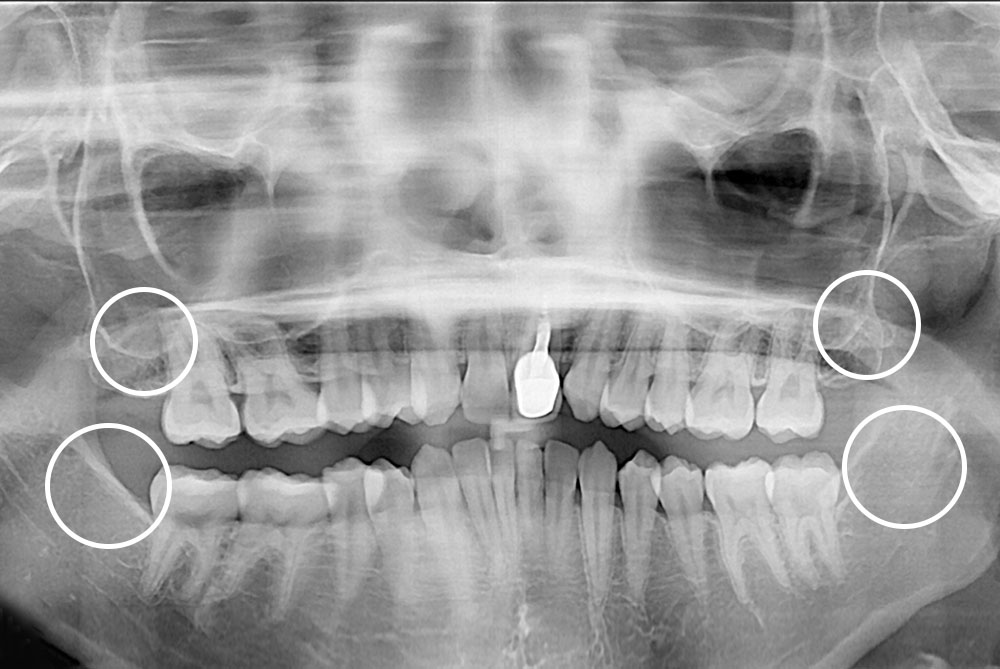

[사랑니] 매복 사랑니 발치

치료전 : 2018-01-18